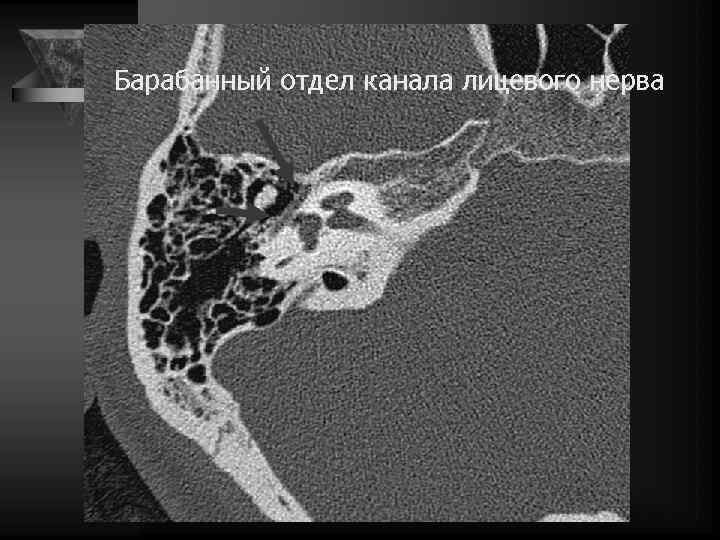

Среднее ухо • Содержимое: потеря воздушности. • Локализация и наличие патол. образований. • Слуховые косточки: вывих, деструкция, анкилоз. • Состояние круглого и овального окна. • Состояние горизонтальной части канала лицевого нерва. • Область расположения коленчатого ганглия. • Барабанная перепонка: утолщена, втянута. • Положение и контуры внутренней сонной артерии, сонного канала. • Положение яремной ямки, состояние луковицы внутренней яремной вены